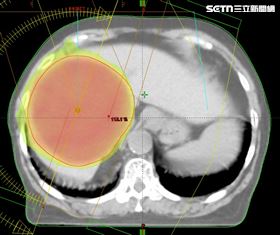

腫瘤指數破千!84歲嬤免挨刀穩控膽管癌

84歲黃阿嬤3年前查出良性肝臟囊腫,後續追蹤卻發現病...

腫瘤如千層派堆疊 醫靠它幫「消腫」

桃園一名80歲唐伯伯本身患有C肝,且定期回診追蹤,但...